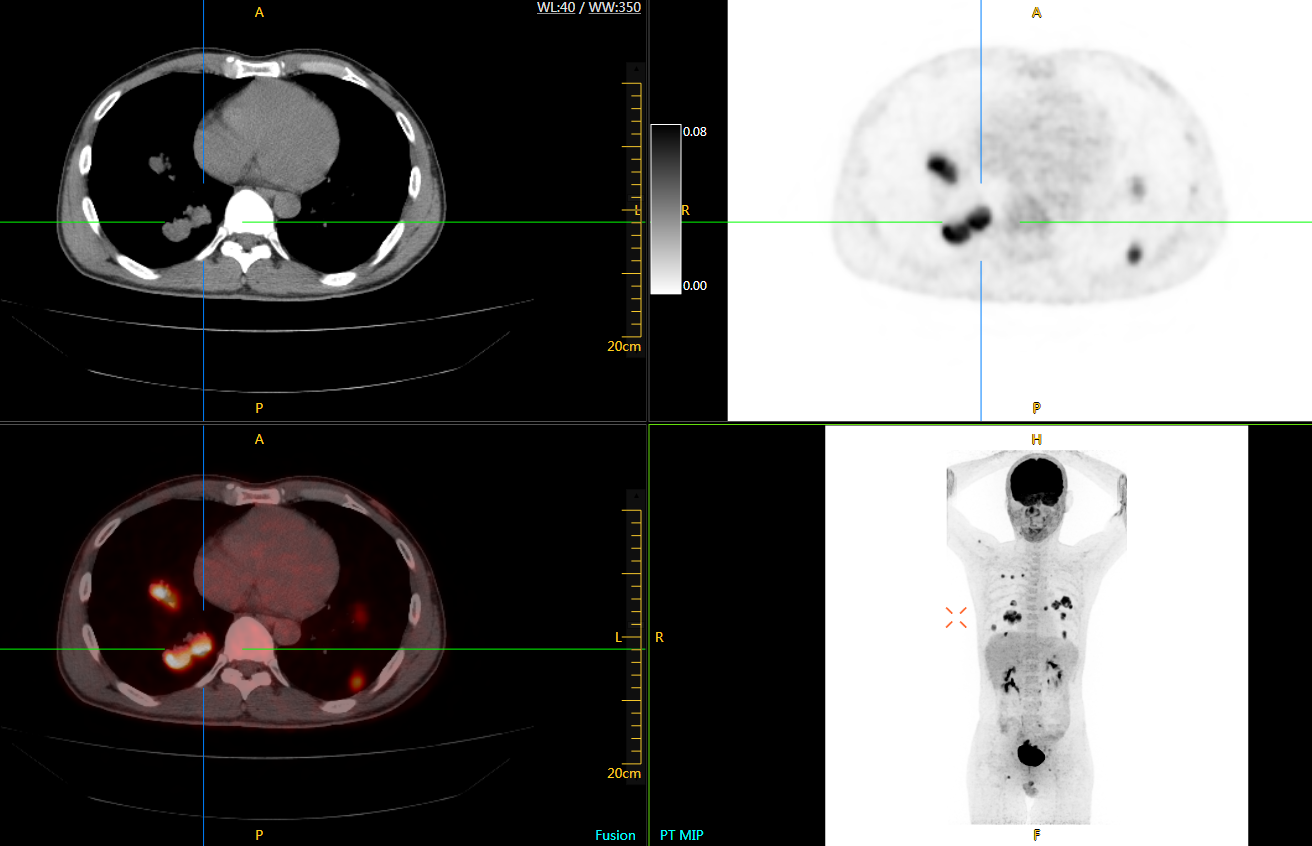

患者男性,66歲,七年前發(fā)現(xiàn)右肺肺癌,其間手術(shù)兩次,共切除兩個肺葉,復查;

診斷意見,回腸轉(zhuǎn)移,右肺殘留部復發(fā)